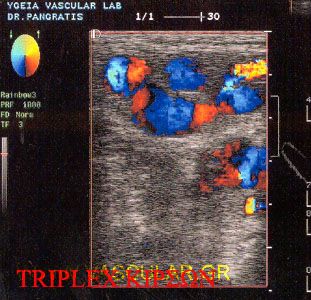

Ç óõóêåõÞ õðåñç÷ùí åã÷ñþìïõ ñïÞò ,( TRIPLEX) ÷ñçóéìïðïéåß probe ãñáììéêÞò äÝóìçò 7,5 MHz ãéá ôá åðéðïëÞò áããåßá Þ 5MHz ãéá ôá åí ôù âÜèåé áããåßá.

Ç Triplex åîÝôáóç ãéá ôçí äéÜãíùóç ôùí öëåâéêþí ðáèÞóåùí ôùí êÜôù Üêñùí áðïôåëåß ôçí êýñéá áíáßìáêôç êáé áîéüðéóôç åîÝôáóç ôïõ öëåâéêïý óõóôÞìáôïò åßíáé áíþäõíç åõêüëùò áðáíáëáìâáíïìÝíç ÷ùñßò êéíäýíïõò ãéá ôïí áóèåíÞ.

Åéò ôï Áããåéïëïãéêü åñãáóôÞñéü óÞìåñá ÷ñçóéìïðïéïýìå ìç÷áíÞìáôá ðñïçãìÝíçò ôå÷íïëïãßáò ðïõ åßíáé éêáíÜ íá ìáò äþóïõí áêñéâåßò ðëçñïöïñßåò ðåñß ôçò êáôáóôÜóåùò ôùí áããåßùí êáé ãéá ôï ôß óõìâáßíåé åíôüò ôïõ áããåßïõ êáèþò åðßóçò ÷ñÞóéìåò ðëçñïöïñßò üóïí áöïñÜ ôçí áéìáôéêÞ ñïÞ.